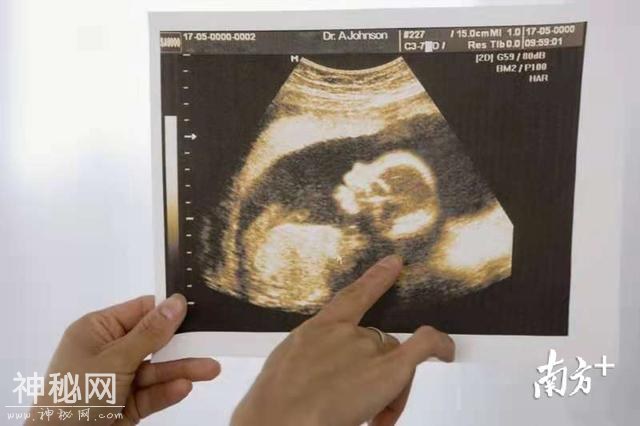

病因找到,梁晓燕和李婷婷马上为小丽进行了系统治疗。只用了短短半年,小丽就顺利怀孕了。看着B超影像里健康发育的宝宝,回想起一路的辛酸苦楚,小丽握着梁晓燕教授的手忍不住落泪。

今年年初,小丽顺利分娩了一个健康的宝宝。整个孕期和产后,梁晓燕教授和李婷婷医生都为小丽提供了细致的健康指导。经过半年多的生长发育监测,目前小丽的宝宝一切正常。